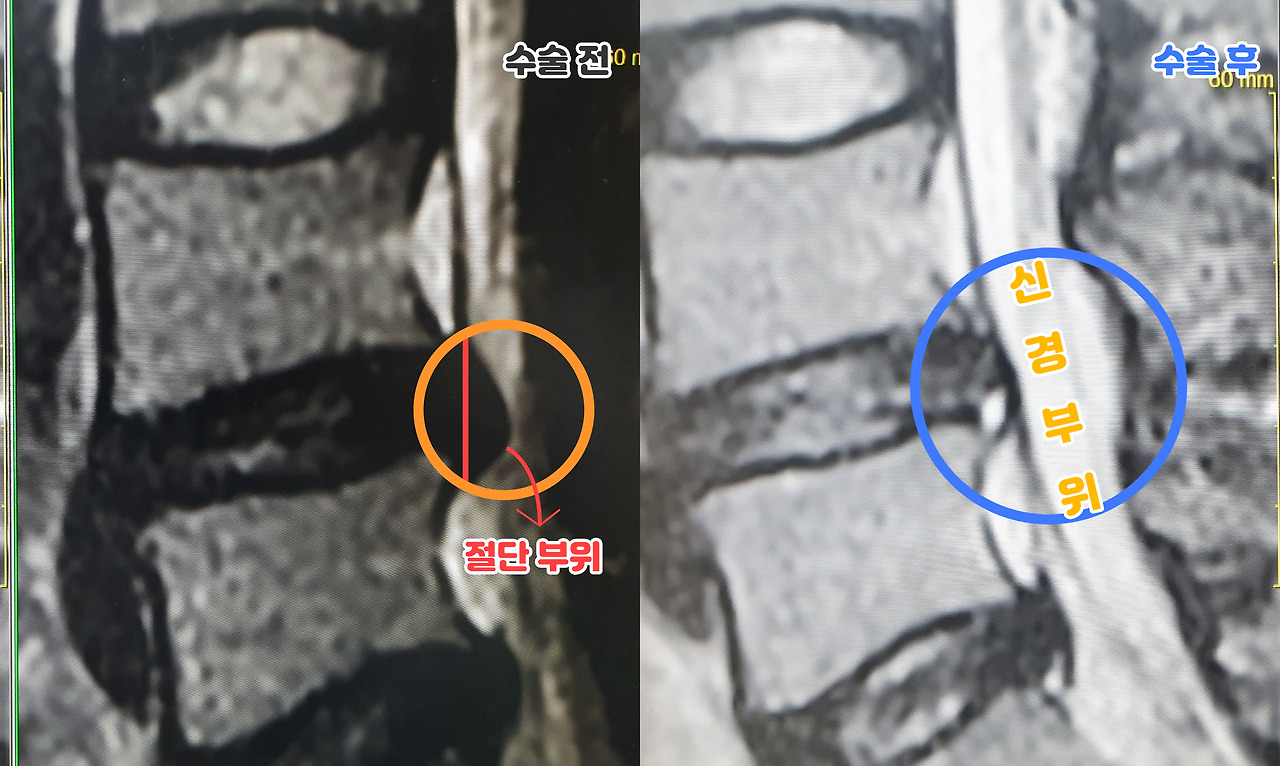

허리디스크-신경.jpg <4번 5번 디스크 사이 돌출부 절단 수술 전 / 후>

지금은 수술한지 3주정도가 되었는데 워낙 상태가 안좋았던터라 오른쪽 통증도 동반되고 있다. 물론 수술 전보다는 훨씬 낫다. 11일 정도를 입원했는데, 누워있는 동안 온갖 생각이 들었다. 허리디스크 터지기 전에 자전거 유튜브를 하고 있었는데, 발병 2주전만해도 전국 국토종주를 완주하면서 컨디션이 상승세를 타고 있었고, 조금 더 본격적으로 타기 위해서 고가의 자전거를 구매했다.